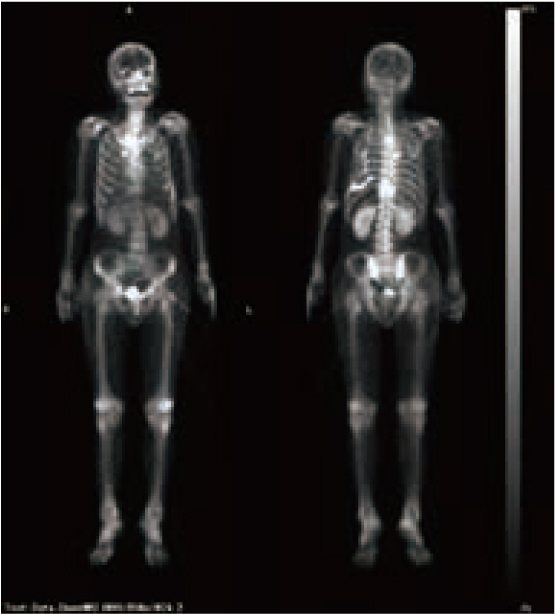

骨シンチ全身像のBSI算出(機能評価の数値化)

骨格の解剖構造認識と高集積部位(ホットスポット)の設定を行い、BSIおよびHS(n)5)を算出します。

画像表示機能(視覚的な情報の提供)

表示スケール(濃度・大きさ・位置)の正規化、高濃度スケールの表示、膀胱等の生理的集積を除いた高集積部位(ホットスポット)の設定および注目度の初期値の付与を行います。